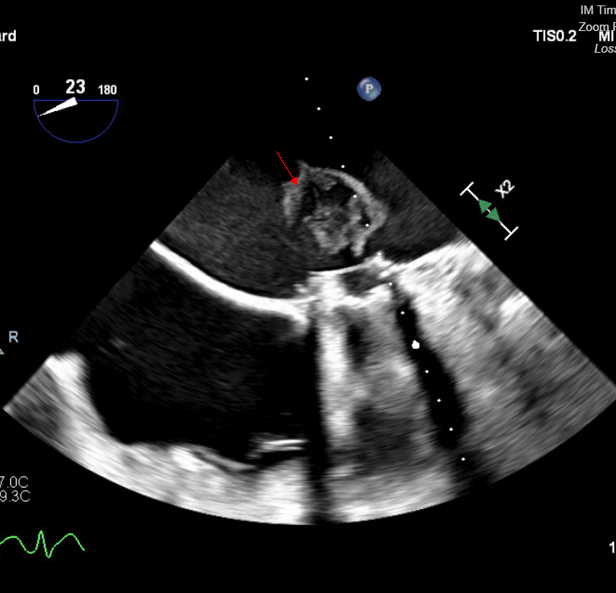

In order to prevent coronary or brain embolization of LAA thrombus, the decision was made to proceed with LAA ligation via the left thoracotomy approach. The patient was then subsequently taken to the operating room for clipping of the LAA with possible cardiopulmonary bypass only if necessary. The LAA was clipped through a left anterior thoracotomy. The patient already had access in her femoral artery and vein for possible institution of cardiopulmonary bypass should it be necessary. A large strand of thrombus was dislodged from the LAA and migrated in the left atrium, obstructing the mechanical mitral valve (Figure 2A-C). The patient was heparinized and placed on cardiopulmonary bypass.